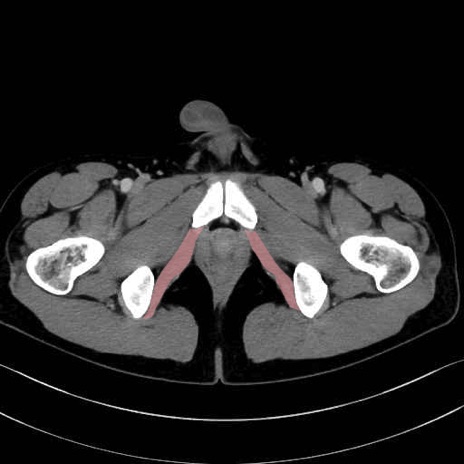

内閉鎖筋 (Obturator internus)